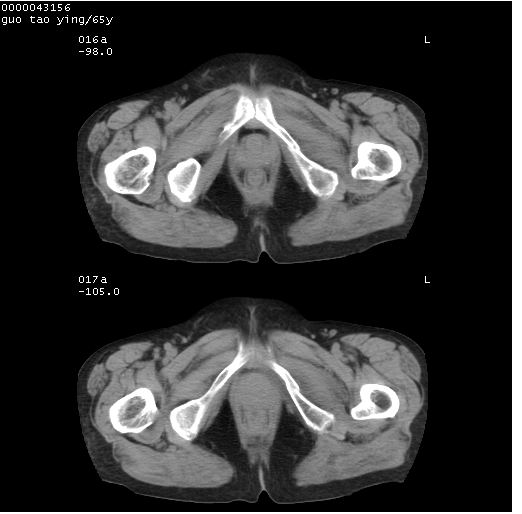

以下是引用黑白光影在2008-1-30 13:22:00的发言:[br]支持左耻骨骨折。[br]未见骶骨骨质明确破坏改变。[br]经楼主提示(勿局限于外伤)。考虑为右侧腹股沟直疝。[br][br][br][br]